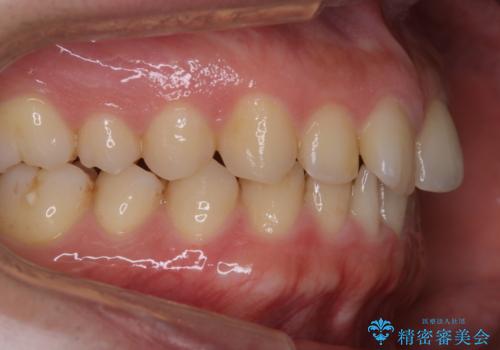

- インビザラインで矯正治療中にクリーニングを希望されました。PMTC60分コースで、クリーニングと歯ブラシ指導を行いました。

磨けているようでも、染出しをして目に見えるプラーク(歯垢)を確認することで、より正しいブラッシング方法を身につけることができます。インビザライン中は、歯にアタッチメントをつけるため、歯の表面がデコボコしてプラークが付きやすい状態になります。毎日のケアでしっかりと汚れを落として虫歯や歯周病・口臭のリスクを減らしていくことが大切です。定期的にメンテナンスを行い、ケアがどれくらい出来ているか確認したり歯科医院で専門的な機械や器具によるPMTCを行うことをおススメします。